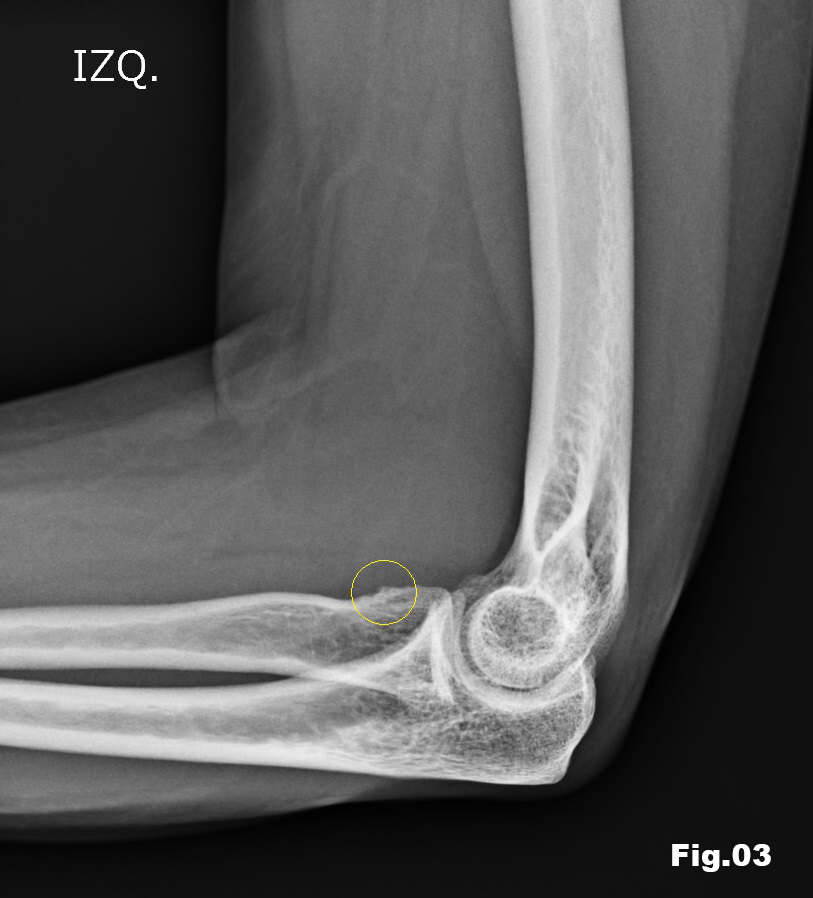

A 51-years-old healthy female, with no history of upper limb injuries, complained of an anterior and proximal left forearm tenderness associated with weakness of the extensor muscles of the forearm. An ultrasound scan was performed and demonstrated a thickened and hypoechoic posterior interosseous nerve (PIN) at the arcade of Frohse, with hypervascularization of the perineurium. In its deeper aspect, there was a subtle irregularity of the radial metaphysis (Fig1,2). The plain film showed a sessile irregularity of the anterior region of the metaphysis (Fig 3). Unenhanced MRI and CT scan were also performed. The CT scan showed the irregularity of the radius (Fig 4) and in the MRI (Fig 5), it was reported as an osteochondroma like metaphyseal lesion of the radius. Initial treatment included a corticosteroid injection around the PIN, but without decrease of symptomatology. The orthopedic surgeon then proceeded with an osteochondroma resection to release the PIN. The upper limb surgical team performed the surgery (Fig 6), and they found a thickened, hyperaemic PIN, adjacent to the osteochondroma (Fig 6,7). They resected the osteochondroma and debrided the PIN (Fig 8). The patient recovered full muscular strength and the tenderness progressively disappeared.

Fig 3: Lateral elbow plain film, showing subtle irregularity of the anterior aspect of the radial metaphysis (circle).